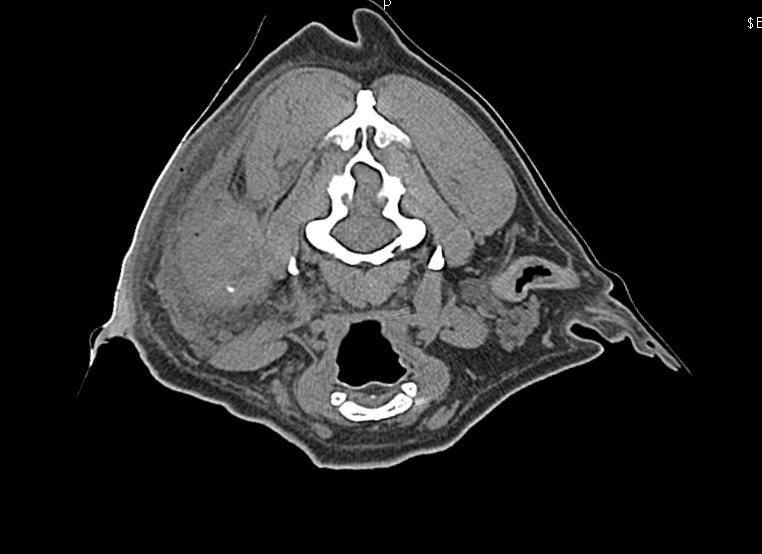

CT検査により外耳から中耳に至る腫瘤の存在が疑われ、耳道軟骨は骨化し、化膿巣は目の下から首にまで達していました。

- 耳道より前の腫れ、目の下にまで広がる

- 外耳道後方の腫れ、頚部にも広がる化膿巣